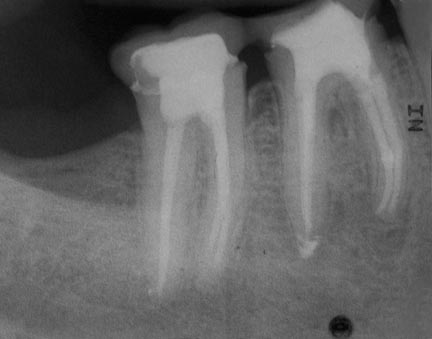

KA-5

432 × 339

Apikale Aufhellung (11,12)